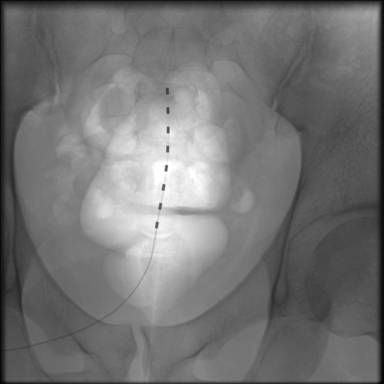

После тщательной обработки операционного поля выполняется небольшой разрез в проекции остистых отростков, на фоне тщательного гемостаза отсепаровыватся паравертебрально поясничная фасция на уровне пункции эпидурального пространства (зависит от уровня неврологического проявления боли). Под углом 45• сагиттально и по направлению к средней линии под местной анестезией иглой Туохи выполняется пункция эпидурального пространства под контролем ЭОП. Также, для контроля попадания в эпидуральное пространство используется шприц низкого давления. При нахожении кончика иглы в эпидуральном пространстве исчезает ощущение резистентости в шприце, жидкость (как правило стерильная вода для иньекций) свободно проходит. Затем по игле вводится проводник для дополнительного контроля свободного проведения электрода. Далее под контролем ЭОП на нужный уровень проводятся электроды. Вид и размер элекродов подбирается в зависимости от задач, решаемых хирургом. Электрод проводится на микропроводниках, входящих в набор и облегчающих установку. Форсированное проведение электрода не рекомендуется. После установки электрода наружная контактная группа присоединяестся кабелем к программатору врача или тестовому стимулятору для подтверждения результатов тестовой стимуляции. При получении положительного результата приступают к монтажу всей системы.

Электроды располагают параллельно ближе к средней линии. При установке одноканальной системы гомолатерально ближе к средней линии. Чем латеральнее друг от друга находятся электроды, тем шире поле воздействия сигнала генератора.

На представленных ниже рисунках отображены основные этапы установки системы.

Установка постоянных электродов

Рентгенконтроль при проведении электродов